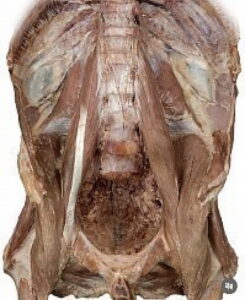

- Mostra organi interni come il fegato, la milza, i reni e lo stomaco.

- Evidenzia la colonna vertebrale (vertebre lombari da L1 a L5) e i muscoli associati come lo psoas.

- Include riferimenti a strutture vascolari come l’aorta e strutture ossee come l’acetabolo.

- Presenta etichette per vari organi pelvici e muscoli, inclusi la vescica e il prostata.

Manca solo l’evidenza dei vasi arterio-venosi e delle innervazioni. Maderu